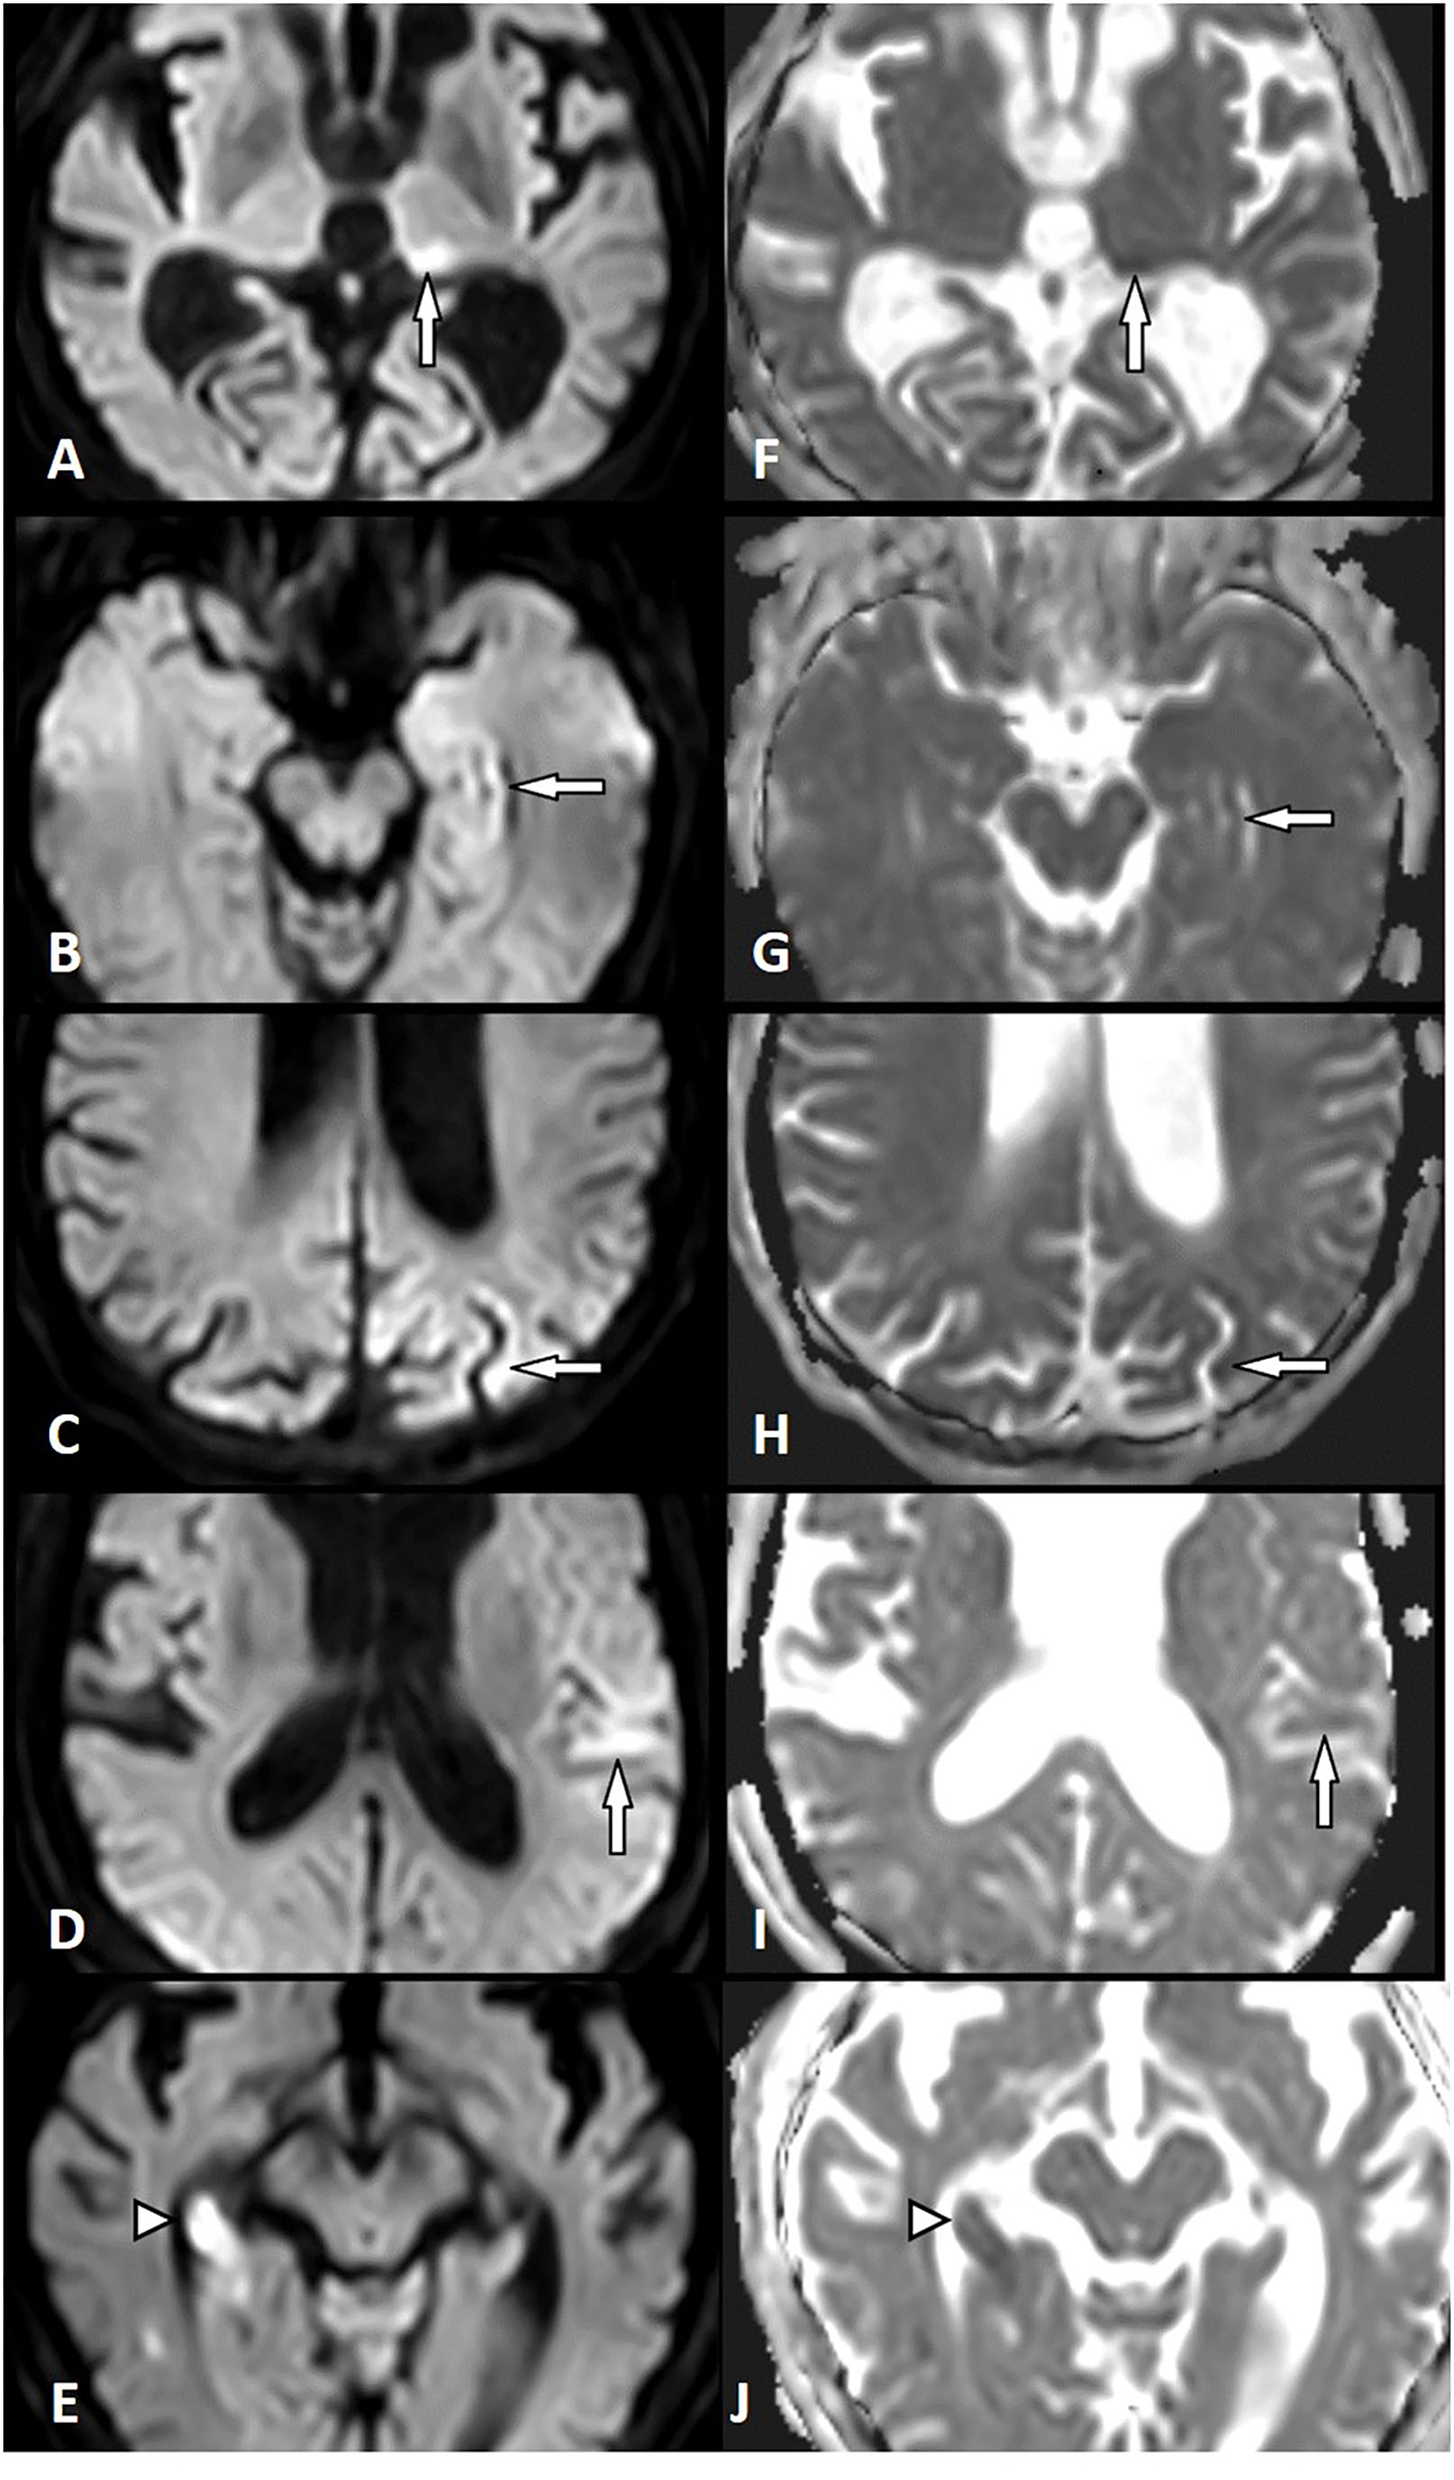

All patients with AIS (n = 164) and SE (n = 26) showed diffusion restriction with hyperintensity in DWI and an ADC signal decrease (Figure 1). However, diffusion restriction was significantly more intense in patients with AIS as compared to patients with SE (Figure 2) with median ratios of the signal intensity for DWI restriction of 1.42 (IQR 1.32–1.47) in SE and 1.67 (IQR 1.49–1.90) in AIS (p < 0.001). ADC signal decrease was more significant in AIS as compared to SE (Figure 2) with median values of ratios of signal intensity −0.80 (IQR 0.72–0.89) vs. 0.61 (IQR 0.50–0.71), respectively (p < 0.001).

Figure 1

Diffusion restriction in status epilepticus (SE) and acute ischemic stroke (AIS). Left column: Diffusion-weighted imaging (DWI). Right column: Apparent diffusion coefficient (ADC). SE-related diffusion restriction in the left pulvinar (A,F), in the left hippocampus (B,G), the left parietal cortex (C,H), and the left temporal cortex (D,I). AIS-related diffusion restriction in the right hippocampus (right posterior cerebral artery territory) (E,J) (white arrow, SE lesion; white arrowhead, AIS lesion).